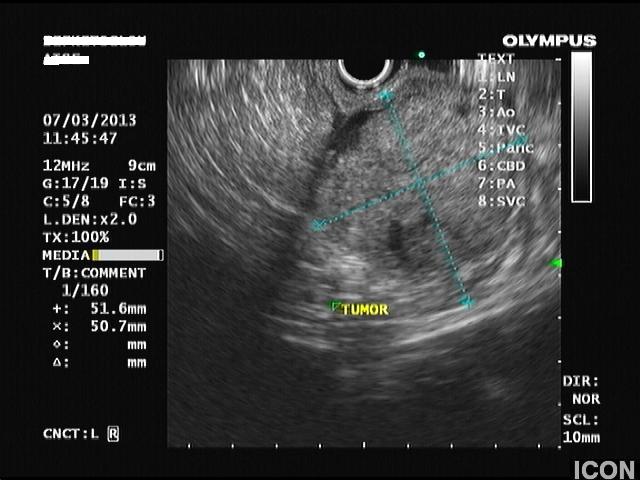

Ο ασθενής υποβλήθηκε σε ενδοσκοπικό υπέρηχο που έδειξε μια υποηχοϊκή μάζα διαμέτρου 21 χιλιοστών, με σαφή όρια, στην παγκρεατική κεφαλή και μεγάλη διάταση του χοληδόχου πόρου και του παγκρεατικού πόρου (διάμετρος 12 χιλιοστά).

Η μάζα είχε ξεκάθαρο διαχωριστικό όριο λίπους από την άνω μεσεντέριο φλέβα και δεν διηθούσε κανένα άλλο μεγάλο αγγείο της περιοχής (πυλαία φλέβα, σπληνοπυλαία συμβολή και αρτηρίες). Έγινε βιοψία με λεπτή βελόνη (FNA Χ3) και το κυτταρολογικό υλικό ήταν θετικό για αδενοκαρκίνωμα παγκρέατος. Το νεόπλασμα κρίθηκε χειρουργήσιμο και ο ασθενής υποβλήθηκε σε επέμβαση Whipple κατά την οποία αφαιρέθηκε πλήρως η παγκρεατική κεφαλή και ο όγκος σε υγιή όρια αλλά και 12 λεμφαδένες που ήταν όλοι αρνητικοί για κακοήθεια. Ο ασθενής υποβάλλεται σε συμπληρωματική χημειοθεραπεία.

Μάζα σώματος παγκρέατος στον ενδοσκοπικό υπέρηχο